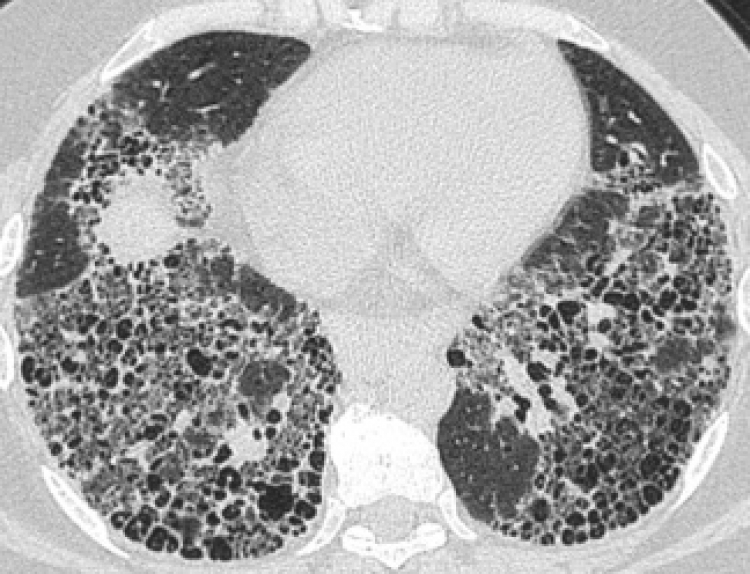

Según el Dr. Omar Barreto Rodríguez, neumólogo especialista en enfermedades pulmonares intersticiales, “la fibrosis pulmonar idiopática es una enfermedad rara que se caracteriza por un proceso anormal y desconocido de cicatrización del tejido del pulmón, lo que provoca una disminución gradual e irreversible de la función pulmonar[2]; es decir, mayor dificultad para respirar y el inadecuado funcionamiento del resto de los órganos a falta de suficiente oxígeno”[3].